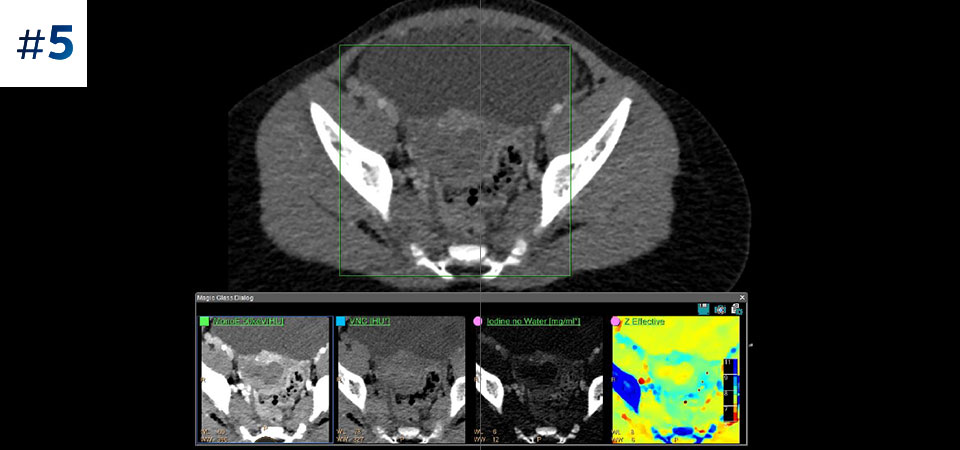

Vá além da CT convencional. Veja de que forma os vários tipos de resultados obtidos com deteção espectral podem aumentar a fiabilidade do seu diagnóstico.

Conheça a diferença entre a CT com detetor espectral e a CT convencional